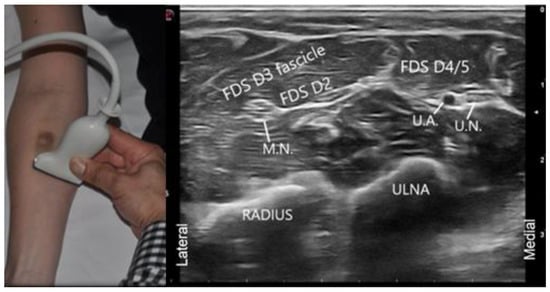

4.5. Visual Ergonomics Using Ultrasound